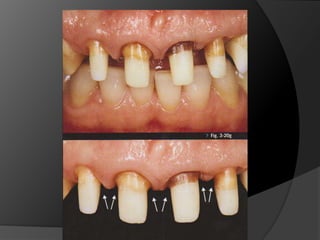

El análisis para seleccionar la ubicación de la línea de terminación se enfoca en 2 componentes:Estética vs HigieneExtensión mínima dentro del surco gingivalDisimular la zona de asentamientoFacilitar la higiene del pacienteNecesidad de aumentar la retención y estabilidadLínea de Sonrisa

PRINCIPIOS ESTÉTICOSRestauraciones con forma, contorno y color adecuados

Reducción AxialCuando la reducción axial es suficiente, las 	paredes de la restauración pueden tener 	un grosor satisfactorio sin sobrecontornos